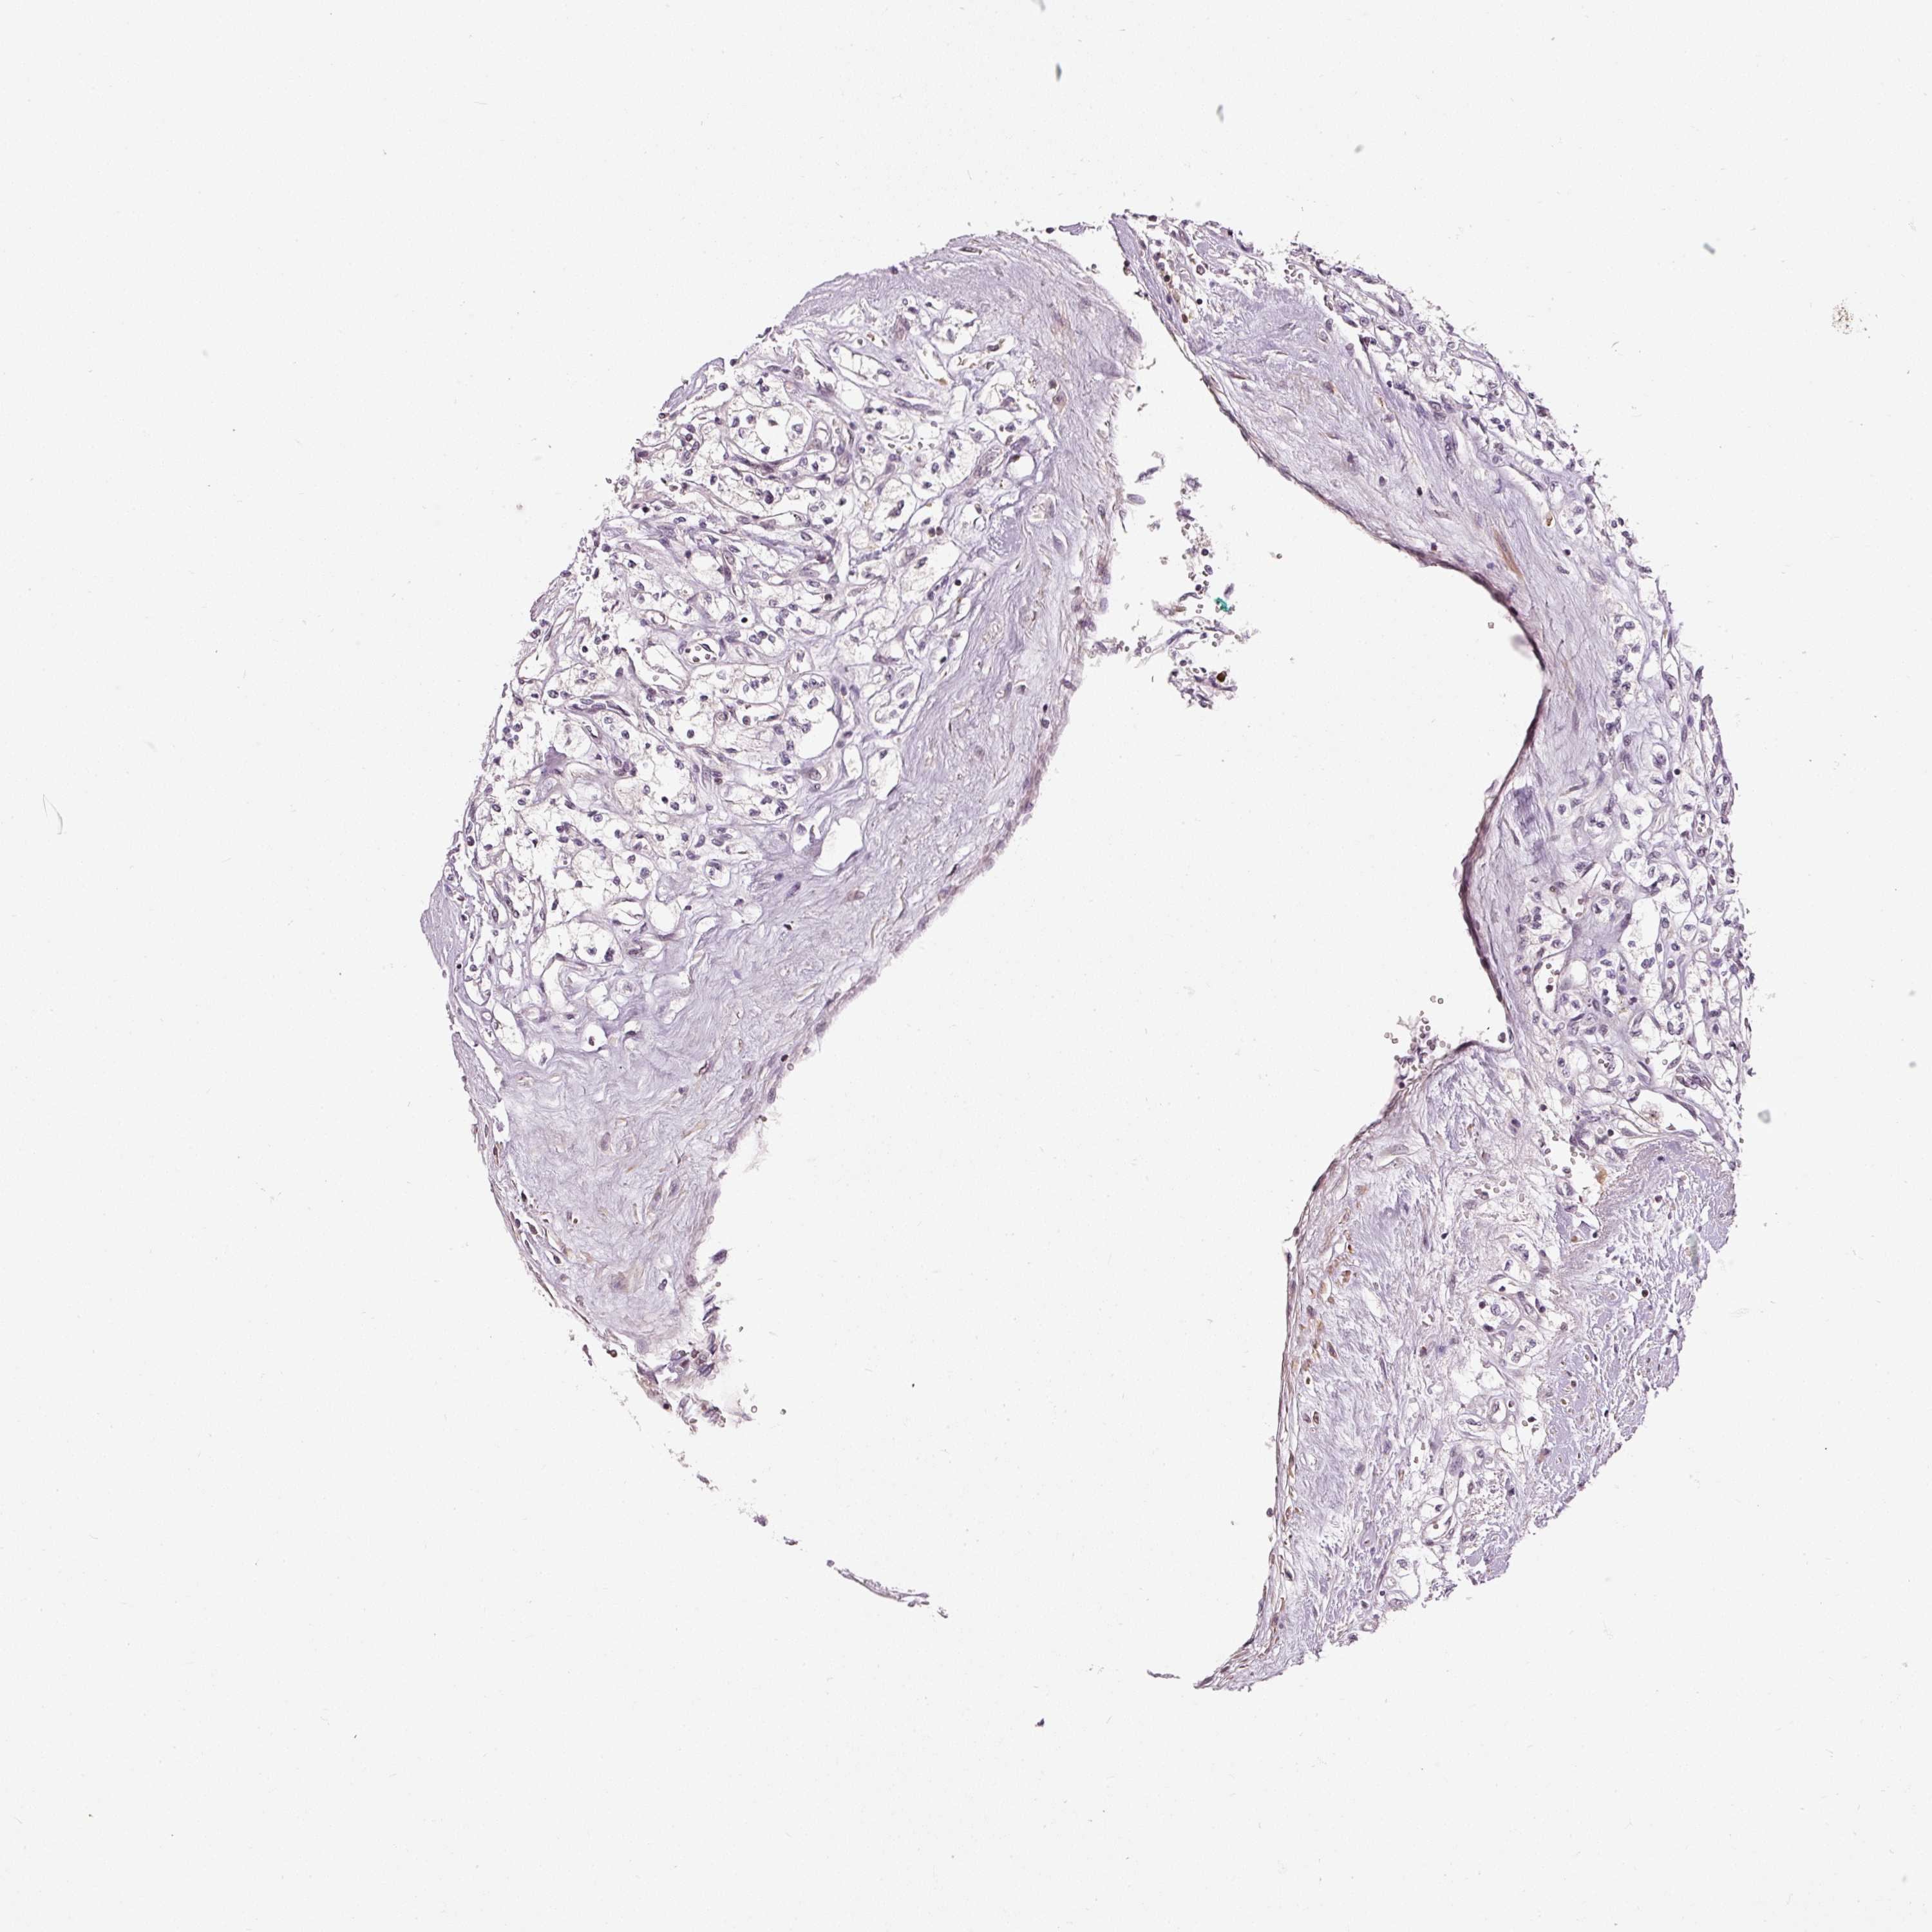

KIDNEY RENAL CLEAR CELL CARCINOMA (VALIDATION) - Interactive survival scatter ploti

The Survival Scatter plot shows the clinical status (i.e. dead or alive) for all individuals in the patient cohort, based on the same data that underlies the corresponding Kaplan-Meier plots. Patients that are alive at last time for follow-up are shown in blue and patients who have died during the study are shown in red.

The x-axis shows the expression levels (FPKM) of the investigated gene in the tumor tissue at the time of diagnosis. The y-axis shows the follow-up time after diagnosis (years). Both axes are complimented with kernel density curves demonstrating the data density over the axes. The top density plot shows the expression levels (FPKM) distribution among dead (red) and alive patients (blue). The right density plot shows the data density of the survived years of dead patients with high and low expression levels respectively, stratified using the cutoff indicated by the vertical dashed line through the Survival Scatter plot. This cutoff is automatically defined based on the FPKM cutoff that minimizes the p-score. The cutoff can be changed by dragging the vertical line or by entering a cutoff value in the square labeled "Current cut-off".

Under the Survival Scatter plot the p-score landscape (black curve; left axis) is shown together with dead median separation (red curve; right axis). Dead median separation is the difference in median mRNA expression between patients who have died with high and low expression, respectively. It is calculated as follows: median FPKM expression of dead patients with high expression - median FPKM expression of dead patients with low expression. This is intended to aid the user in visually exploring custom cutoffs and the associated p-scores and dead median separation.

Individual patient data is displayed and can be filtered by clicking on one or more of the category buttons on the top of the page. Categories describing expression level and patient information include: high, low, alive, dead, female, male and tumor stages. The scale of the x-axis can be toggled between linear and log-scale by clicking on the "x log" button. Mouse-over function shows TCGA ID, patient information and mRNA expression (FPKM) for each patient.

& Survival analysisi

Kaplan-Meier plots summarize results from analysis of correlation between mRNA expression level and patient survival. Patients were divided based on level of expression into one of the two groups "low" (under cut off) or "high" (over cut off). X-axis shows time for survival (years) and y-axis shows the probability of survival, where 1.0 corresponds to 100 percent.

THOC6 is not prognostic in Kidney Renal Clear Cell Carcinoma (validation)

Best expression cut offi

Based on the FPKM value of each gene, patients were classified into two groups and association between prognosis (survival) and gene expression (FPKM) was examined. The best expression cut-off refers the FPKM value that yields maximal difference with regard to survival between the two groups at the lowest log-rank P-value. Best expression cut-off was selected based on survival analysis .

When clicking on this number, the vertical dashed line indicating cut-off, the interactive survival plot, and the Kaplan-Meier curve will be adjusted to show results based on the best expression cut-off.

: 24.42

TCGA RNA samplesi

RNA-seq data is reported as average FPKM (number Fragments Per Kilobase of exon per Million reads), generated by the The Cancer Genome Atlas (TCGA) .

Normal distribution across the dataset is visualized with box plots, shown as median and 25th and 75th percentiles. Points are displayed as outliers if they are above or below 1.5 times the interquartile range. FPKM values of the individual samples are presented next to the box plot.

Average pTPM 27.4

Number of samples 100